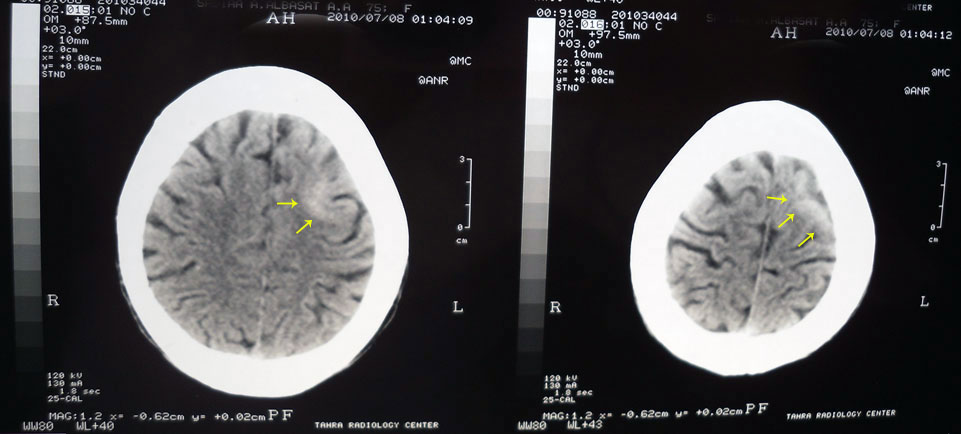

A 74 year-old female, diabetic, complained of

unilateral right upper limb fits that became generalized.

CT And MRI brain ordered with the above photos results.

Left high parietal subcortical lesion with mass effect manifested as

effacement of the adjacent sulci, mostly neoplastic mass lesion for

better assessment by enhanced MRI study.